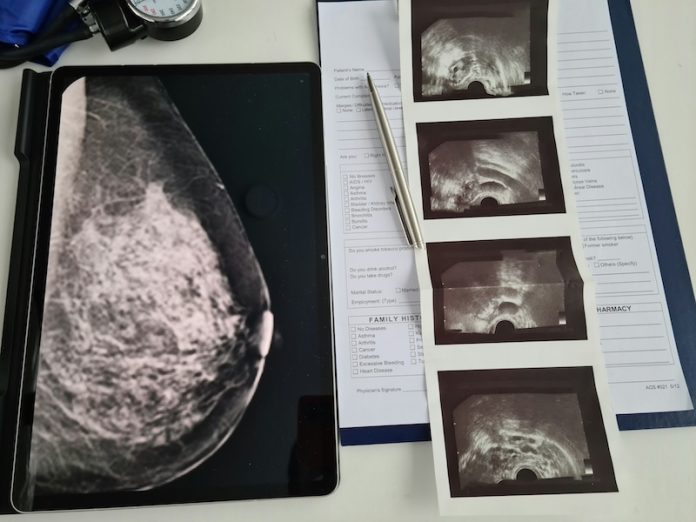

Mammograms are commonly used to find breast cancer, but new research shows they might also reveal important signs of heart disease—the number one cause of death for adults.

Researchers found that the amount of calcium in the breast arteries, which shows up on mammograms, can be a warning sign of future heart problems.

Calcium in arteries is a sign that the blood vessels are becoming stiff and unhealthy. Usually, doctors use a CT scan to check for calcium in the heart’s arteries, but these scans can be expensive and expose patients to more radiation.

Mammograms, on the other hand, are already recommended for women starting at age 40 and are much more common. So using mammograms to check for heart disease risk might be a smart way to use existing tests for more than one purpose.

The researchers used special computer software with artificial intelligence to check how much calcium was in the arteries in the breast and how much it had changed over time.

The researchers gave each mammogram a score for calcium build-up. Women were placed into four groups: no calcium, mild, moderate, and severe. About 19% of the women had some calcium in their arteries at the beginning. Those with more calcium had a higher chance of a heart-related problem in the future.

This study is one of the first to show that calcium in breast arteries can grow over time and that faster growth means higher risk. The findings suggest that doctors could use mammograms not just to find cancer but also to check for heart disease risk in women.